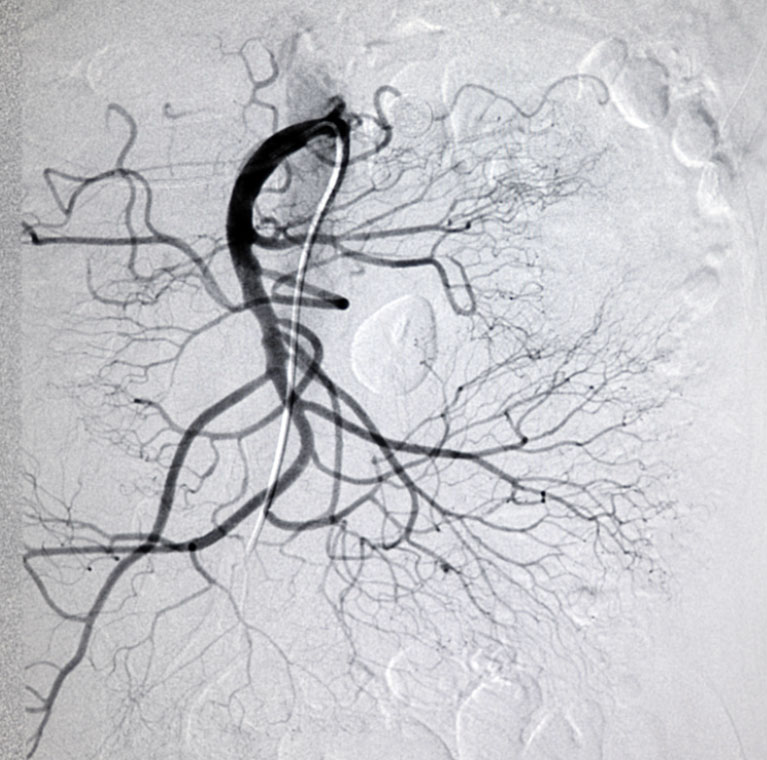

Image

Mesenteric Arteries

(CT Scan)